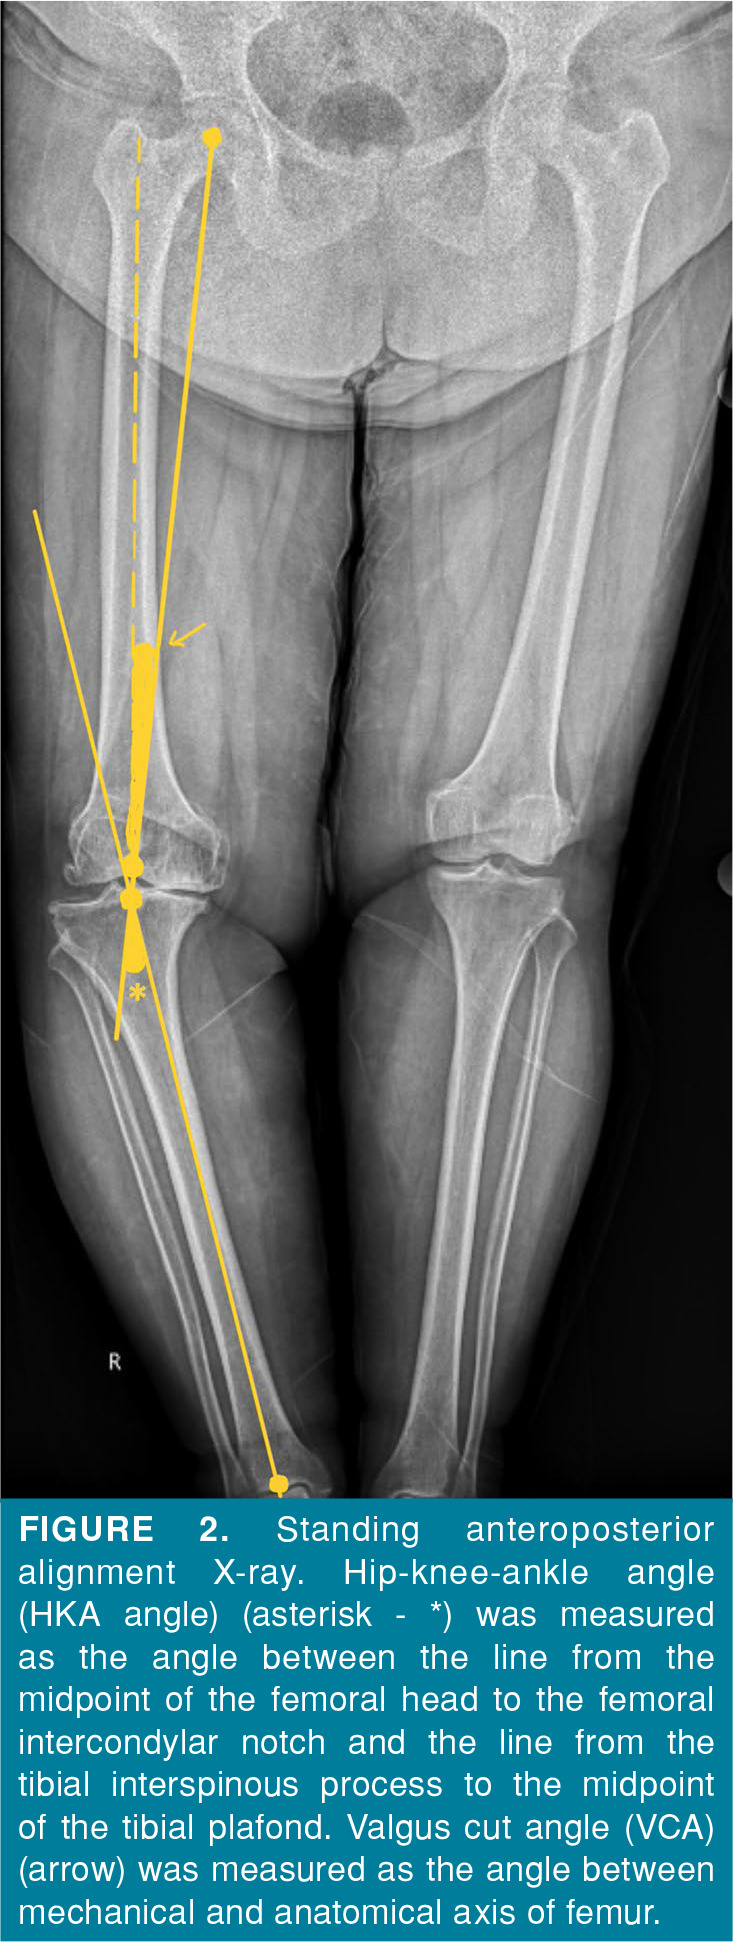

Objectives: This study aims to compare the radiographic results with and without postoperative metal augmentation in varus knee patients with primary total knee arthroplasty (TKA) with a hip-knee-ankle (HKA) angle >10° and to determine a cut-off value using radiographic parameters to predict the need for metal augmentation.

Patients and methods: Between October 2022 and April 2024, a total of 87 knees (51 right and 36 left) of 82 patients (11 males, 71 females; mean age: 68.7±8 years; range, 53 to 86 years) who underwent primary TKA were retrospectively analyzed. The patients were divided into two groups as patients who underwent primary TKA with and without tibial metal augmentation. There were 39 patients and 42 knees in the group with metal augmentation and 43 patients and 45 knees in the group without metal augmentation. The HKA angles and amount of preoperative planned tibial resection (ETR) were evaluated. Cut-off values for preoperative HKA angle and ETR were determined using receiver operating characteristic (ROC) analysis.

Results: The mean pre- and postoperative HKA angles were 18.98±4.42° and 6.58±3.48°, respectively and the mean ETR was 13.91±3.02 mm. Both groups were comparable in terms of postoperative HKA angles p=0.283). The mean preoperative HKA and ETR were significantly higher in TKAs with augmentation (p<0.001 for both). The probability of needing augmentation was approximately six times higher in knees with a preoperative HKA angle of >20.6° (OR=5.909, 95% CI: 2.065-16.91, p<0.001) or ETR of >12.52 mm (OR=5.816, 95% CI: 2.202-15.359, p<0.001).

Conclusion: In TKA with advanced varus deformity, tibial metal augment is a method that can be used to provide soft tissue balance. The need for metal augmentation should be kept in mind, particularly if the preoperative evaluation indicates that the HKA angle exceeds 20.6° or ETR exceeds 12.5 mm.